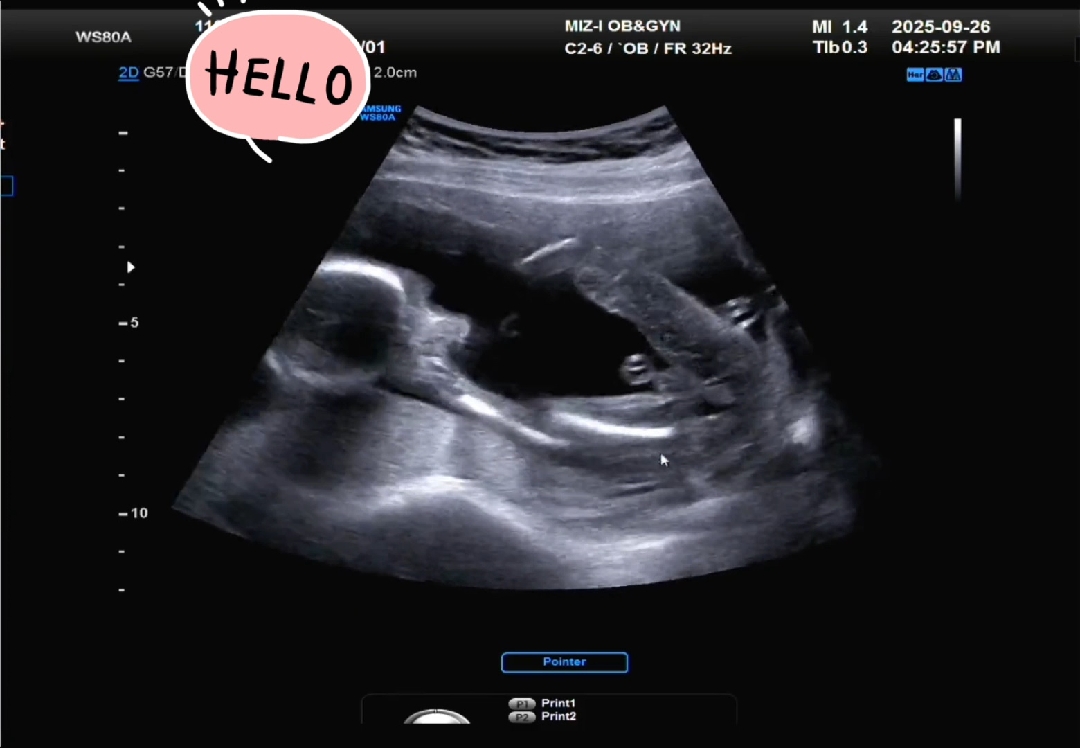

18주성별! 아들이라고 하시는데 맞을까요?

안녕하세요^^ 임신한지 18주된 맘이에용 어제 산부인과 갔는데 원장님께서 아들이라고 하시더라고요~ 그런데.. 저는 잘 안보여서ㅠ초산모라 그런지 초음파가 잘 안보이네용 ㅠ성별반전있을까싶어.. 잘 보시는 분들께 여쭤보려고 사진올립니다! 보시고 답 부탁드려용🙂

저도 초산인데 아들맘인데 아들같아용